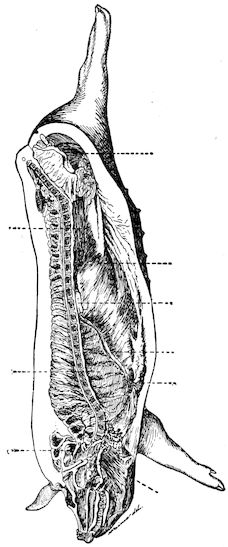

Fig. 2.—Horse suffering from osseous cachexia.

2. The second phase is characterised by more precise signs, which become almost pathognomonic. Difficulty in rising is added to the already existing tendency to remain lying, and to the interference with movement.

When lying down the patient no longer responds to the trifling stimulus, which a healthy animal needs to cause it to rise. It remains languid and apparently lazy, though in reality it experiences pain and difficulty on attempting to get up. The least muscular effort when lying down often causes it to moan, as do efforts to change its position or to walk. Even when standing still, it may appear to be in pain, and patients often assume a position similar to that of a horse suffering from laminitis.

At the end of this second phase, swellings appear, due to synovitis or arthritis of the extremities, synovitis of the sesamoid or navicular sheaths or to inter-phalangeal arthritis or arthritis of the fetlock joint. Weakness becomes marked, and the appetite is very irregular.

10Secretion of milk diminishes or ceases and abortion is not uncommon.

3. The third phase is characterised by fractures, and it is this peculiarity of the disease which has procured for it the names of fragilitas ossium, and osteoclastia. These fractures may affect any portion of the skeleton. Animals so suffering sometimes break a leg whilst trotting or the pelvis in simply jumping over a ditch; a collision with a fixed object like the jamb of the stable door, or a fall on the ground, may result in the fracture of one or several ribs.

Fig. 3.—Pig suffering from osseous cachexia (fourth stage).

Such shocks would be of no importance to a healthy animal, but to one suffering from osseous cachexia, any violence, or even the slightest muscular effort may be followed by fracture of the gravest character, involving even the vertebral column. In cows the pelvis, femur, and tibia are most frequently injured.

In horses, particularly in riding horses, fractures are commonest in the region of the forearm, cannon bone, and anterior phalanges. So extremely fragile are the bones at this stage that the horse represented herewith broke twelve ribs at one time by simply falling on its side. It is interesting to note that such fractures are never accompanied by any extensive bleeding. They have little tendency to repair, no real callus formation occurs, and on post-mortem examination one often finds the ends unconnected by temporary callus, worn, and rounded by reciprocal friction.

At this stage but under other circumstances, the animals show great reluctance to rise, remaining down for twelve to twenty-four hours without shifting their position. If forced to get up, they stand as though fixed in one position, the respiration and circulation become rapid, and they soon grow tired and fall.

In horses, the different phases of the disease develop precisely as in bovines. The apparent differences between affected horses and cattle result in reality from differences in their capacity for continuing work. In the first phase, horses are incapable of work, their movements being 13badly co-ordinated. They are inclined to stumble, and appear as though suffering from strain of the lumbar muscles.

In the second phase pain referable to the bones sets in. Lameness develops without visible lesions and is rapidly followed by synovitis and arthritis in the lower portions of the limbs, and by wasting and anæmia.

The animals seem unable to move rapidly, or if forced to do so may sustain fractures even at a trot: the limb bones sometimes break or ligamentous insertions in the neighbourhood of joints are torn away, resulting in sudden falls on the ground and fracture of ribs or even of the vertebral column. This corresponds to the third phase, osteoclastia, in oxen.

Fig. 6.—Osseous cachexia. This condition developed in two months, the last month of gestation and the first of lactation.

From then onwards, horses become useless and, if not destroyed, may, after a few weeks or months, develop the condition known as osteomalacia, in which the flat bones become softened, the head, the branches of the lower jaw and the face become deformed, while mastication and other functions are impeded.